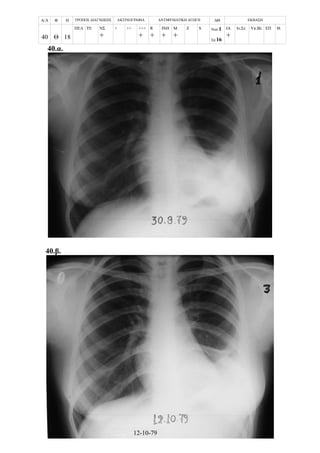

Περίπτωση 16η:

Α/Α Φ Η ΤΡΟΠΟΣ ΔΙΑΓΝΩΣΗΣ ΑΚΤΙΝΟΓΡΑΦΙΑ ΑΝΤΙΦΥΜΑΤΙΚΗ ΑΓΩΓΗ ΔΘ ΕΚΒΑΣΗ

16 Θ 10

ΠΕΛ ΤΕ ΝΣ

+

+ ++ +++

R

ΙΝΗ

Μ

Z S Νοσ.

Σπ.12

ΙΑ

Ιν.Στ. Υπ.Βλ ΕΠ Θ.

16.α. Επαφή

16.β.

3/3/1987

10-03-87

16.γ.

16.δ.

10/3/1987

18/5/1987

16.ε.

16.στ.

25/8/1987

9/6/1988